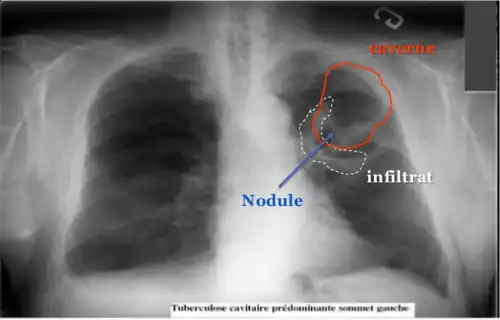

La modalité de diagnostic radiologique se révèle très utile et indiquée comme étant un examen de première intention en cas de tuberculose pulmonaire et ostéoarticulaire[78]. Cela est justifié par les images radiologiques plus ou moins spécifiques à la tuberculose. La littérature rapporte que la spécificité varie de 27 à 81 % selon l’étude. Les imageries idéales et révélatrices de la tuberculose répondent à certains attributs dont le premier est lié au siège. En raison de l’affinité que les BK ont envers les régions aérées, la lésion radiologique est souvent observée dans les parties hautes des poumons. Néanmoins, l’image radiographique peut contenir différentes formes :

- infiltrat : traduisant des lésions débutantes de l’infection via une opacité peu dense, hétérogène et étendue ;

- nodule : granulome de taille variable, isolé ou groupé ;

- tuberculome : nodule isolé pseudotumoral ;

- caverne : excavation par perte de substance au sein d’un infiltrat, aux parois épaisses.

Les cavernes sont une complication fréquente de la tuberculose pulmonaire[55]. On appelle caverne une cavité creusée au sein du parenchyme pulmonaire[56]. Les bacilles tuberculeux se développent initialement dans le poumon sous forme de nodules, appelés granulomes, qui sont peu à peu entourés de lymphocytes et de macrophages destinés à contenir l'infection[55]. Un granulome peut évoluer soit vers la disparition sans cicatrice, soit vers la caverne, sans que les mécanismes sous-jacents soient compris en totalité[56]. Les vestiges de macrophages détruits occupent le centre du granulome et forment la majeure partie de la nécrose caséeuse[56]. Chez certains patients, cette nécrose caséeuse se liquéfie et devient un milieu de culture adapté aux bacilles, qui prolifèrent. Des enzymes protéolytiques érodent alors la capsule fibreuse située en périphérie du granulome, et son centre liquide peut alors se vider peu à peu[56]. Lorsqu'une caverne tuberculeuse arrive en communication avec l'arbre bronchique, la dissémination des bacilles dans l'air expiré augmente la contagiosité[55],[57]. Par ailleurs, la quantité importante de bacilles contenus dans les cavernes favorise le développement de résistances aux anti-tuberculeux[57].